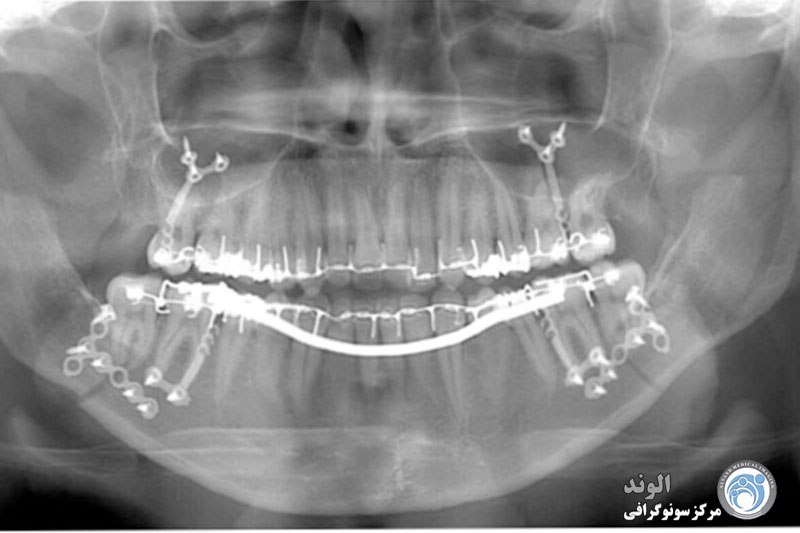

همچنین، OPG برای پیگیری روند درمانهای طولانیمدت، مانند ارتودنسی یا بازسازی استخوان، بسیار مفید است. با مقایسه تصاویر در طول زمان، پزشک میتواند پیشرفت درمان را ارزیابی کرده و در صورت نیاز تغییراتی در برنامه درمانی ایجاد کند. به طور کلی، تصویربرداری OPG یک ابزار دقیق و همهجانبه است که هم به تشخیص بهتر مشکلات دهانی کمک میکند و هم در طراحی درمانهای مؤثر و ایمن نقش اساسی دارد.

پس از هر گونه مداخله اساسی بر روی دندان های بیمار، انجام ارتوپانتوموگرام جدید توصیه می شود تا همیشه آخرین نمای پانوراما از دندان ها و فک های بیمار در پرونده بیمار وجود داشته باشد.

اشعه ایکس پانورامیک از مقادیر بسیار کمی تابش برای کمک به گرفتن کل دهان در یک تصویر دو بعدی استفاده می کند. این اشعه ایکس در کارهای روزمره دندانپزشکی استفاده می شود و بیمار را در معرض کمترین اشعه ممکن قرار می دهد و در عین حال تصویری را که برای ارائه مراقبت با کیفیت به بیمار نیاز دارد به دندانپزشک ارائه می دهد. این اشعه ایکس به عنوان آمادهسازی برای پروتزهای مصنوعی، بریسها، کشیدن دندان، و ایمپلنتها استفاده میشود تا مواردی را که دندانپزشکان از آنها استفاده میکنند نام ببرند.